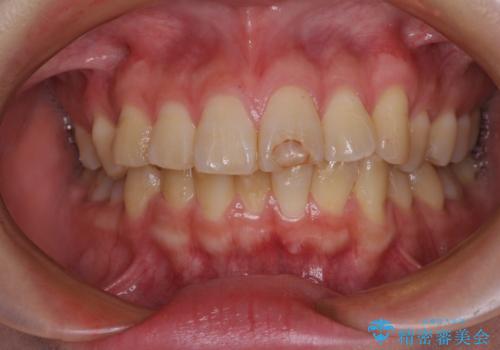

- ぶつけて欠けてしまった前歯を樹脂でつめていたものの、すり減りや変色が顕著とのことで来院された患者様です。

詰め物の詰め直しとオールセラミッククラウンの双方をご提案し、患者様ご希望によりオールセラミッククラウンにて補綴治療を行うこととしました。

歯列全体に表面の着色があったため、クリーニングとホワイトニングを事前に行い、ホワイトニング後1ヶ月ほどおいて、色の落ち着いたところで色合わせを行いました。